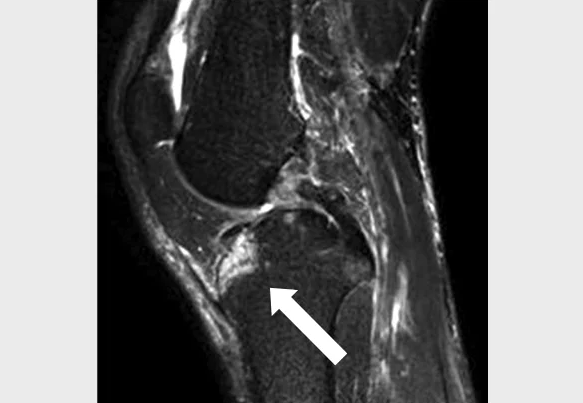

PCL Injuries